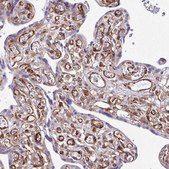

• IHC tissue array of 44 normal human tissues and 20 of the most common cancer type tissues.

Scientific reports, 12(1), 12186-12186 (2022-07-17)

The extracellular activity of Plasminogen activator inhibitor-1 (PAI-1) is well described, acting as an inhibitor of tissue plasminogen activator and urokinase-type plasminogen activator, impacting fibrinolysis. Recent studies have revealed a pro-tumorigenic role of PAI-1 in human cancers, via the regulation